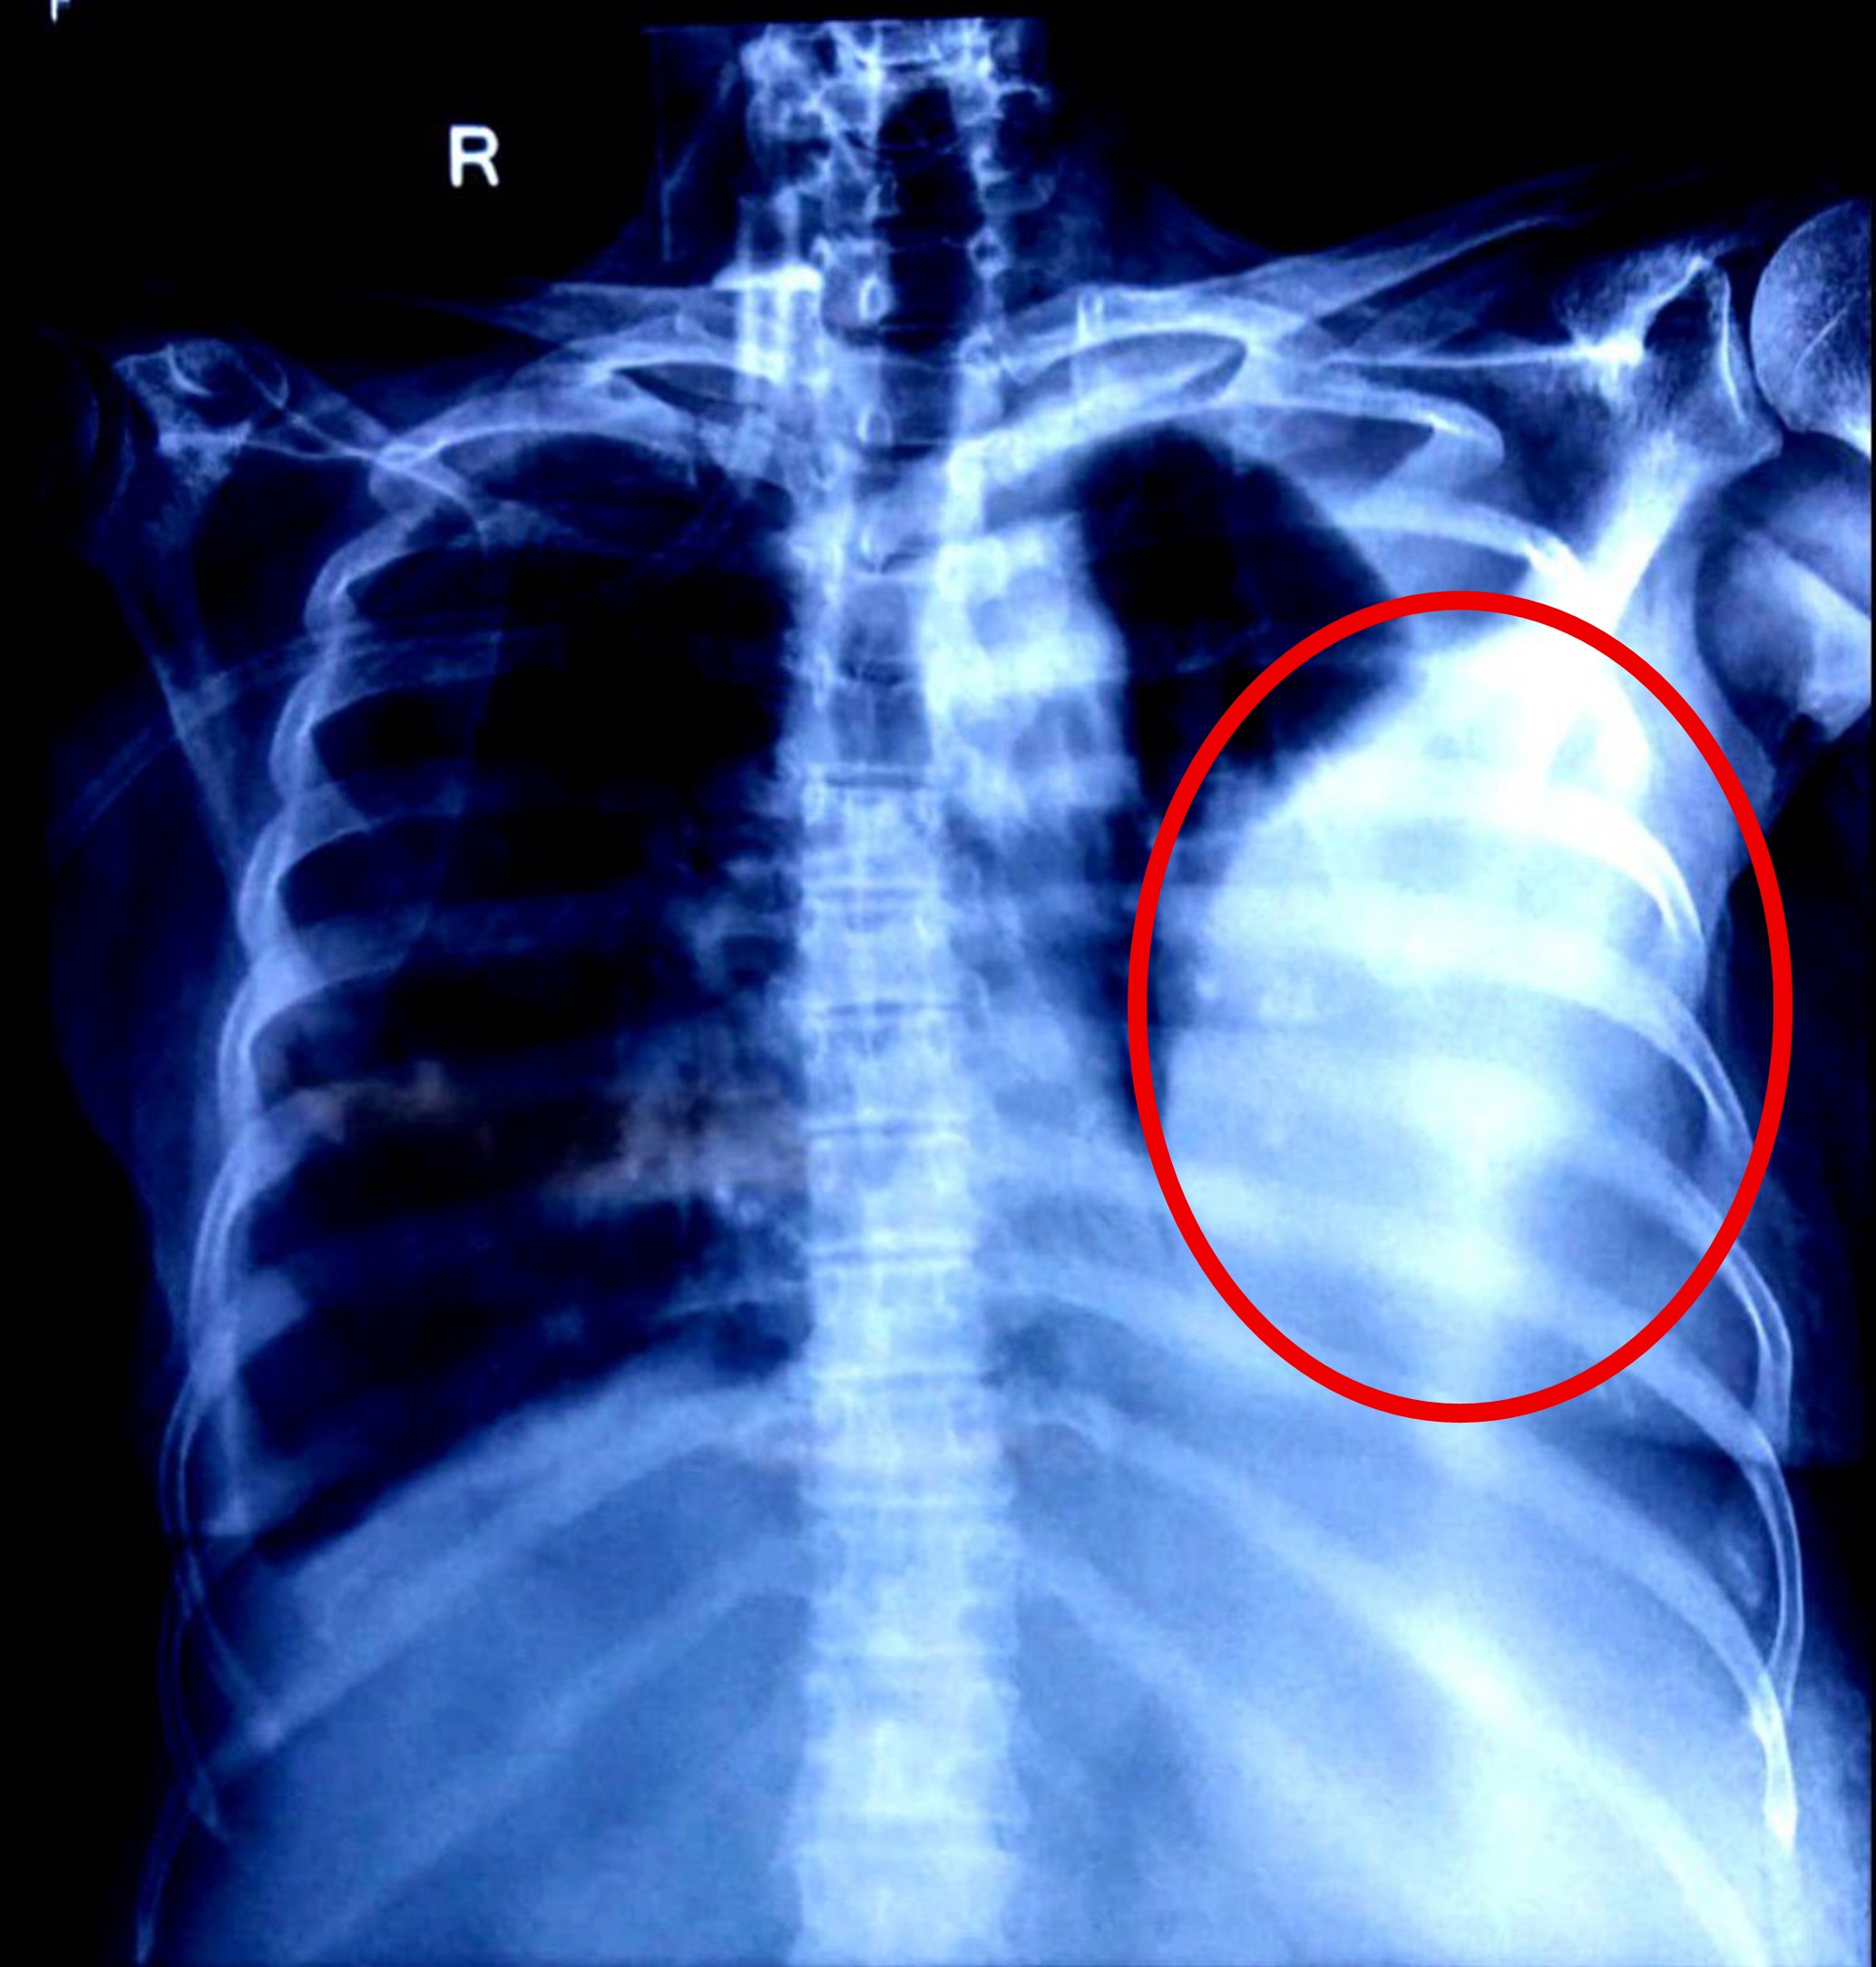

- Chest X-ray AP (June 9, 2025, and June 11, 2025): Both radiographs consistently demonstrated the presence of significant pleural effusion, correlating with her respiratory symptoms.

1. Impaired gas exchange related to altered oxygen supply (pleural effusion, ascites compressing diaphragm) and hypoventilation as evidenced by breathlessness, orthopnea, and abnormal chest X-ray findings.